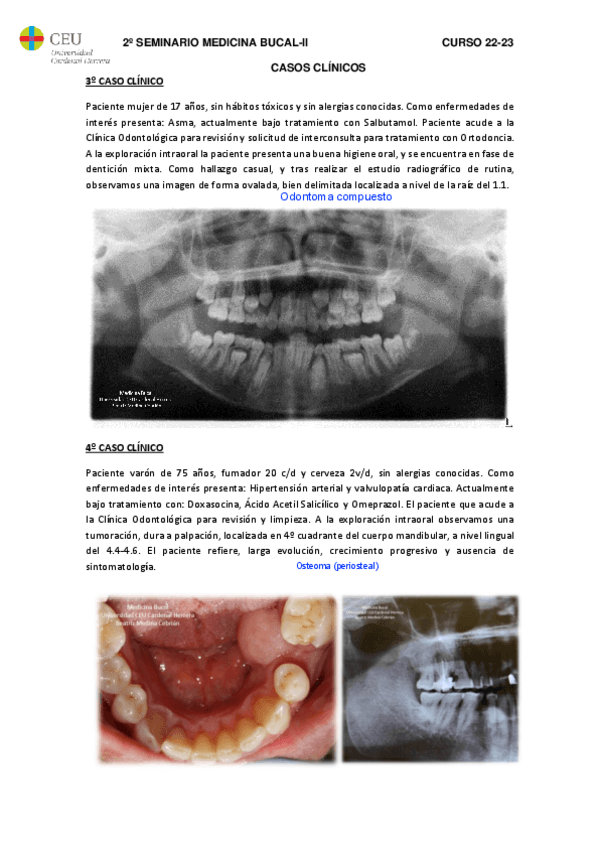

He publicado nuevos examenes de 3º Medicina Bucal II: 2o-SEMINARIO-MEDICINA-BUCAL-II-CASOS-CLINICOS.pdf

5 páginas